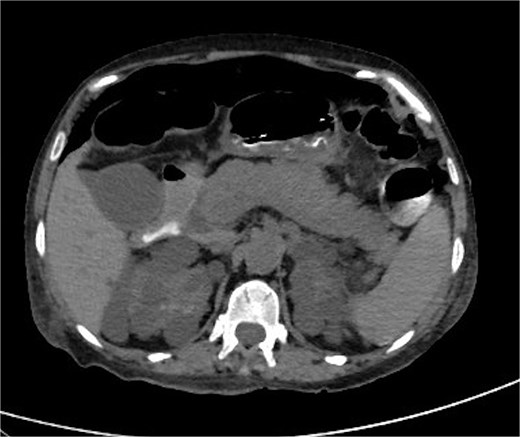

Chest X-ray revealed pneumoperitoneum (Fig. 1), and computed tomography (CT) scan confirmed free intraperitoneal air with no evident abscess (Fig. 2). The patient was admitted to the intensive care unit, resuscitated, and underwent urgent exploratory laparotomy.

CT scan of abdomen and pelvis: pneumoperitoneum and polycystic disease in the kidneys, liver, and pancreases.